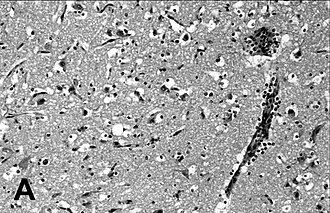

imunohistokemijsko bojenje pluća tuljana s PDV‑om | |